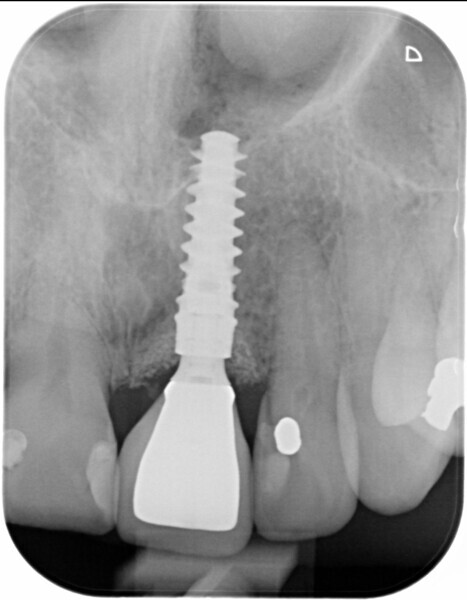

Fig. 11: Final implant position assessment.

Fig. 19: Periapical radiograph to confirm temporary abutment gingival height.

Fig. 29: Periapical radiograph one week post-op.

Fig. 33: Final result radiograph.